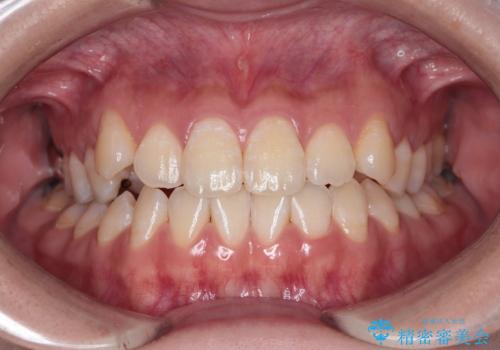

【インビザラインとワイヤー矯正】がたつきと噛み合わせを改善!